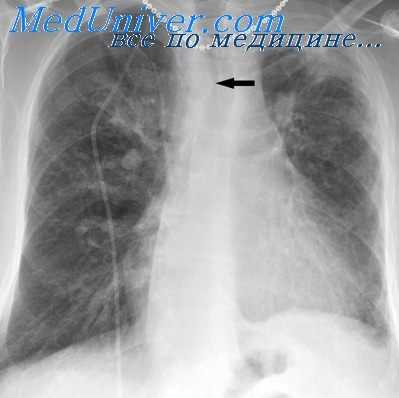

Диагностика легочной гипертензии без применения катетеризации полостей сердца трудна. Однако имеются косвенные клинические симптомы ее при различных врожденных пороках сердца. У детей раннего возраста отмечаются выраженный двусторонний сердечный горб, разлитой сердечный толчок, акцент и раздвоение II тона над легочной артерией, передаточная пульсация эпигастральной области, склонность к повторным пневмониям, сердечная недостаточность, гипертрофия желудочков, отставание в росте и весе.

Диагноз подтверждается данными рентгенологического и инструментальных методов исследования: фонокардиографией, электрокимографией, реовазографией и катетеризацией полостей сердца (Rudolf, Cayler, 1958; В. И. Бураковский, Б. А. Константинов, 1964; Ю. Д. Волынский с соавт., 1967, и др.).

При выраженной легочной гипертензии исчезают характерные симптомы порока, уменьшается или исчезает шум, появляется цианоз, сначала непостоянный, при физической нагрузке, а затем и в покое, увеличиваются симптомы сердечной недостаточности, нарушается газообмен в легких. Такие больные жалуются на быструю утомляемость, одышку при незначительной физической нагрузке, сердцебиение и боли в области сердца, головные боли. Периодически могут наблюдаться носовые или легочные кровотечения. В дальнейшем присоединяется тяжелая декомпенсация, протекающая по правожелудочковому типу.